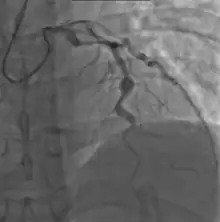

- Angiography was historically used to detect coronary artery aneurysms, and remains the gold standard for their detection, but is rarely used today unless coronary artery aneurysms have already been detected by echocardiography.